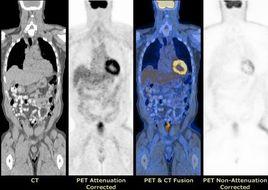

PET/CT則是將PET和CT(計算機體層顯像)有機結合在一起,使用同一個檢查床和同一個圖像處理工作站,將PET圖像和CT圖像融合,可以同時放映病灶的病理生理變化和形態結構,明顯提高診斷的準確性。

三 、 PET-CT的圖像融合

PET與CT兩種不同成像原理的設備同機組合,不是其功能的簡單相加。而是在此基礎上進行圖像融合,融合後的圖像既有精細的解剖結構又有豐富的生理.生化功能信息 能為確定和查找腫瘤及其它病灶的精確位置 定量、定性診斷提供依據。並可用X線對核醫學圖像進行衰減校正。

PET-CT的核心是融合,圖像融合是指將相同或不同成像方式的圖像經過一定的變換處理 使它們的空間位置和空間坐標達到匹配,圖像融台處理系統利用各自成像方式的特點對兩種圖像進行空間配準與結合, 將影像數據註冊後合成為一個單一的影像。 PET-CT同機融合(又叫硬體融合、非影像對位)具有相同的定位坐標系統,病人掃描時不必改變位置,即可進行 PET-CT同機採集, 避免了由於病人移位所造成的誤差。採集後兩種圖像不必進行對位、轉換及配準,計算機圖像融合軟體便可方便地進行

2D、3D的精確融合,融合後的圖像同時顯示出人體解剖結構和器官的代謝活動, 大大簡化了整個圖像融合過程中的技術難度、避免了複雜的標記方法和採集後的大量運算, 並在一定程度上解決了時間、空間的配準問題, 圖像可靠性大大提高。

PET在成像過程中由於受康普頓效應、散射、偶然符合事件、死時間等衰減因素的影響, 採集的數據與實際情況並不一致, 圖像質量失真,必須採用有效措施進行校正,才能得到更真實的醫學影像。同位素校正得到的穿透圖像系統解析度一般為12 mm、而 X線方法的穿透圖像系統解析度為1mm左右 圖像信息量遠大於同位素方法。用 CT圖像對 PET進行衰減校正 使 PET圖像的清晰度大為提高,圖像質量明顯優於同位素穿透源校正的效果(請看圖2), 解析度提高了 25%以上,校正效率提高了 30%,且易於操作。校正後的 PET圖像與 CT圖像進行融合, 經信息互補後得到更多的解剖結構和生理功能關係的信息 對於腫瘤病人手術和放射治療定位具有極其重要的臨床意義。